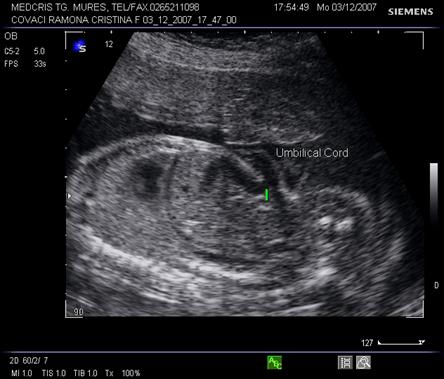

Fig. nr. 187. Cordon ombilical cu trei vase sangvine , in sectiune transversala ( sageata)